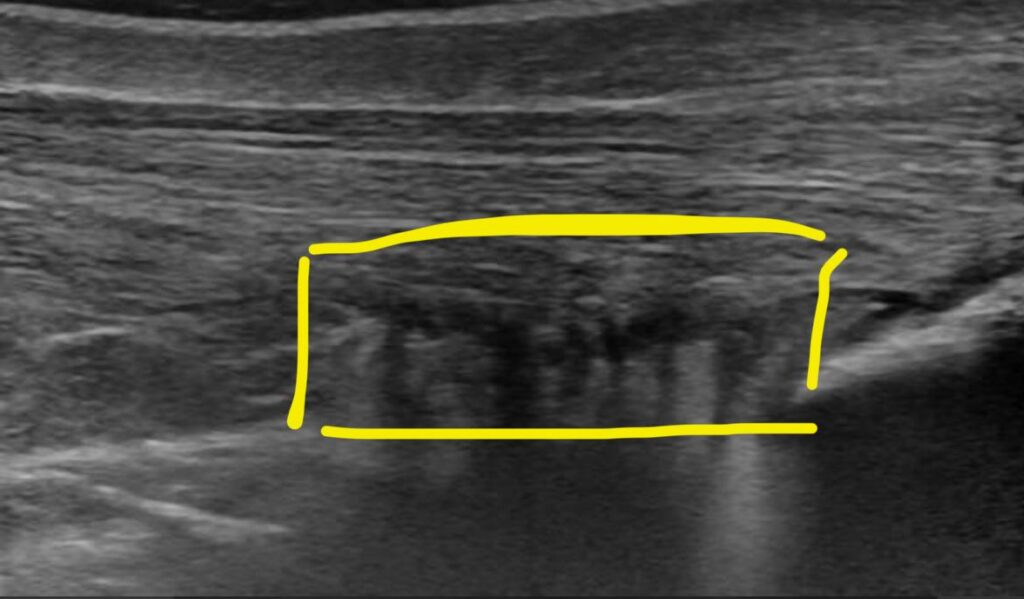

Por otro lado, podemos ver esta imagen de otro paciente también operado hace 3 meses por una rotura del tendón. Al igual que antes, a la izquierda el tendón se encuentra en reposo y a la derecha durante una flexión plantar activa contra resistencia.

A diferencia de lo esperado en un tendón funcional, durante la contracción las fibras aparecen onduladas y sin tensión, al igual que las suturas quirúrgicas visibles en la imagen. Esto indica que el movimiento no se realiza gracias al tríceps sural, sino probablemente por la acción compensatoria de otros flexores plantares. El tendón, en este caso, se comporta como una estructura elongada y funcionalmente ineficaz.